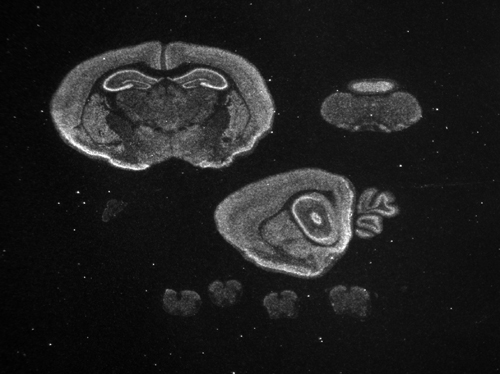

Specimen

g01105 P7:

postnatal day 7

| Structure |

Level |

Pattern |

Image |

Note |

| TS28: basal ganglia |

Present |

Regionally restricted |

| TS28: brainstem |

Widespread |

| TS28: cerebellum |

| TS28: choroid plexus |

| TS28: hypothalamus |

| TS28: midbrain |

| TS28: main olfactory bulb |

| TS28: retina |

| TS28: spinal cord |

| TS28: thalamus |

| TS28: amygdala |

Strong |

| TS28: cerebral cortex |

| TS28: hippocampus |

| TS28: meninges |

Absent |